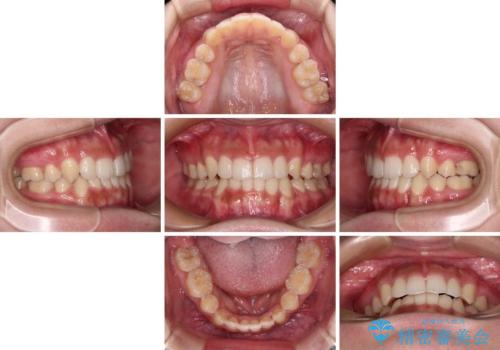

- 顕著な八重歯が気になるとのことで来院された患者様です。

インビザラインでの治療を希望されましたが、インビザライン単独では困難と判断されたため、補助装置や一部ワイヤー装置を用いて行うこととしました。

叢生が強いため、上下左右第一小臼歯4本を抜歯することとしました。